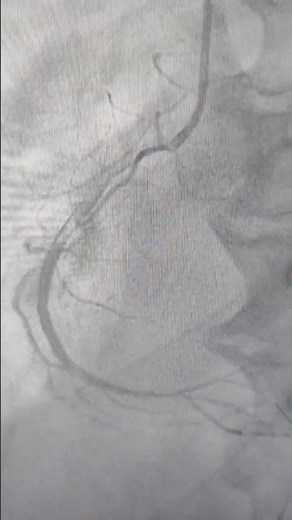

Primary PTCA to RCA

YouTube

INFUSION MEDICAL &

已浏览 52 次

2 个月之前

INFUSION MEDICAL & EDUCATION ZONE (I…